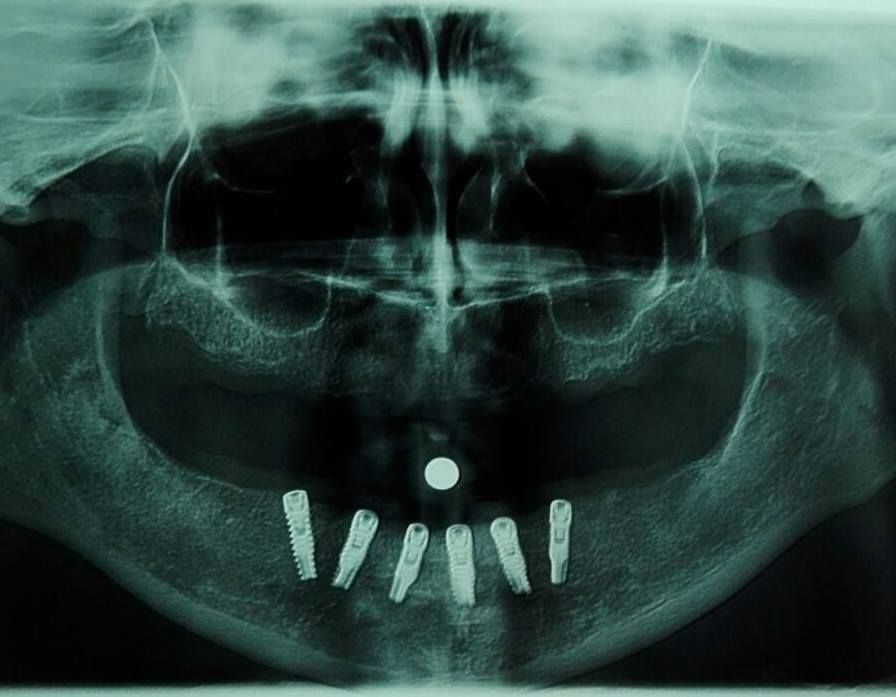

Lo Studio Dentistico Dott. Murruni Giuseppe a Giussano, in provincia di Monza e Brianza, propone percorsi di implantologia per la sostituzione degli elementi dentari persi. L’implantologia è una branca dell’odontoiatria il cui obiettivo è sostituire i denti mancanti mediante l’inserimento nell’osso mandibolare o mascellare di radici artificiali in titanio, chiamate impianti dentali endossei.

Su queste radici artificiali viene poi applicato un manufatto protesico, spesso una corona, realizzata su misura per imitare estetica e funzione del dente naturale. Il titanio è un materiale biocompatibile: grazie anche a superfici opportunamente trattate, stimola un processo di guarigione ossea chiamato osteointegrazione, cioè una vera e propria “fusione” tra impianto e osso. Questo processo richiede un tempo medio compreso fra due e quattro mesi, variabile in base alla situazione clinica.

La protesi Toronto avvitata su 5 ò 6 impianti, cosi chiamata perche presentata per la prima volta a Toronto, permette di realizzare una protesi fissa in brevissimo tempo, che comprende una intera arcata, con pochi passaggi alla poltrona, e in alcuni casi selezionati, in presenza di osso di buona qualità, anche con carico immediato contestuale all’inserzione degli impianti.

La protesi All-on 4 del Dott. Malò consente di caricare contestualmente all’inserzione degli impianti , che in questo caso sono tassativamente solo quattro, una protesi completa immediata e fissa con notevole soddisfazione funzionale, economica e anche estetica del paziente.